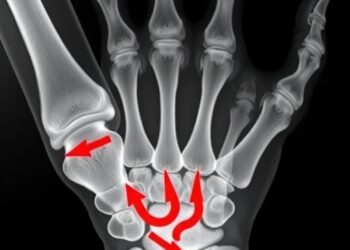

AR Osteotomy Guide for Malunited Distal Radius Fractures